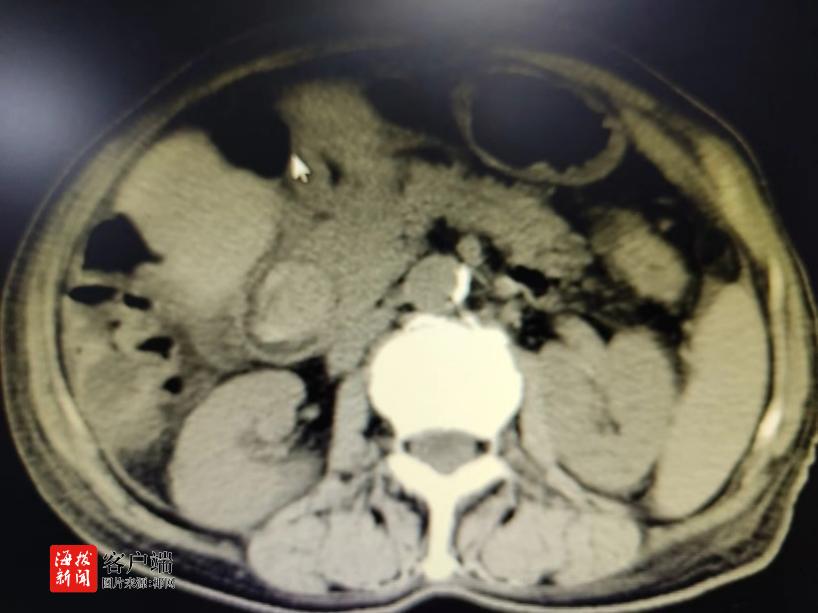

商报全媒体讯(椰网/海拔新闻记者 孙鑫 通讯员 邓佳列)近期,一位83岁高龄、身患多种基础疾病且胆总管被巨大结石(2.8cm×3.0cm)困扰的患者,在多方求医无果后,最终在海南医学院第一附属医院消化内科找到了希望。经过精心策划和精湛技术,该院消化内科成功为她实施了ERCP胆总管取石术,让她摆脱了病痛的折磨。

毛女士,一年来反复被上腹部疼痛所困扰。她多次住院被诊断为胆总管结石并感染,辗转了多家医院,尝试了各种治疗方法,但因高龄且基础疾病较多——合并有冠心病(冠状动脉中重度狭窄,其中回旋支狭窄90%)、心律失常、心脏瓣膜病(主动脉中重度关闭不全),高血压病、凝血功能异常等,且胆总管结石巨大(2.8cm×3.0cm),手术及麻醉风险极高,均未能成功取石。